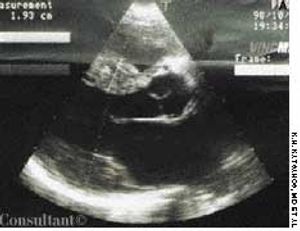

Dyspnea, orthopnea, and weight loss sent a 40-year-old woman for medical consultation. Fifteen years earlier, the patient had been nephrectomized because of left kidney lithiasis. There was no history of other symptoms or diseases.